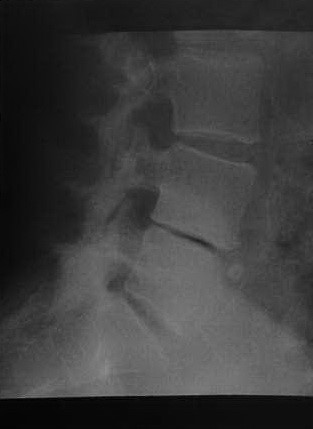

Женщина 58 лет с выраженным остеохондрозом L4-L5. Рентгенологическое исследование поясничного отдела позвоночника демонстрирует потерю высоты межпозвонкового диска с реактивным, полулунного участка склероза кости непосредственно рядом с замыкательной пластиной позвонка. Вакуумный феномен в межпозвонковом пространстве. Случайная находка в области L5 (передняя грыжа диска). Остеоартрит суставных поверхностей L4-S1.